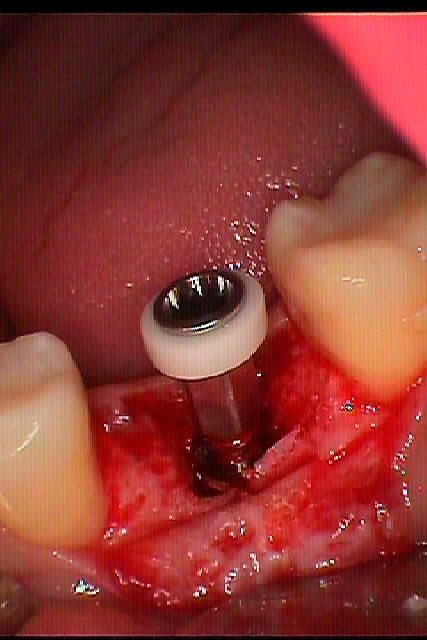

左下6番噛むと痛む 診てほしい |お知らせ |広島市安佐南区の歯科医院 左下6番噛むと痛む 診てほしい トップ お知らせ・ブログ お知らせ 左下6番噛むと痛む 診てほしい 左下6番噛むと痛む 診てほしい この歯が痛む歯になります デンタルレントゲンでは近心根が大きく病巣を形成し 保存不能 中は割れていました パーフォレーションもありました 保存不能により抜歯 ブリッジかインプラントかお話をしまして インプラントとなりました インプラント埋入時になります 縫合して終了 次の日になります Web診療予約 初めての方へ 選ばれ続ける理由 院内設備について 歯が痛いしみる一般歯科 歯がぐらぐらする歯周病 健康な歯を保ちたい予防歯科 子供の虫歯予防をしたい小児歯科 銀歯をセラミックに審美歯科 白い歯を目指しませんか?ホワイトニング 矯正専門医がいるので安心矯正歯科 抜けた歯を補いたいインプラント・入れ歯 医院案内 スタッフ紹介 メリィハウス歯科クリニックオフィシャルホームページ ラベンダー歯科クリニックオフィシャルホームページ お知らせ・ブログ ホーム 診療科目 一般歯科 歯周病治療 予防治療 小児歯科 審美治療 ホワイトニング 矯正歯科 入れ歯・インプラント マウスピース矯正 初めての方へ 院長・スタッフ 設備紹介 医院案内・アクセス メニューを閉じる